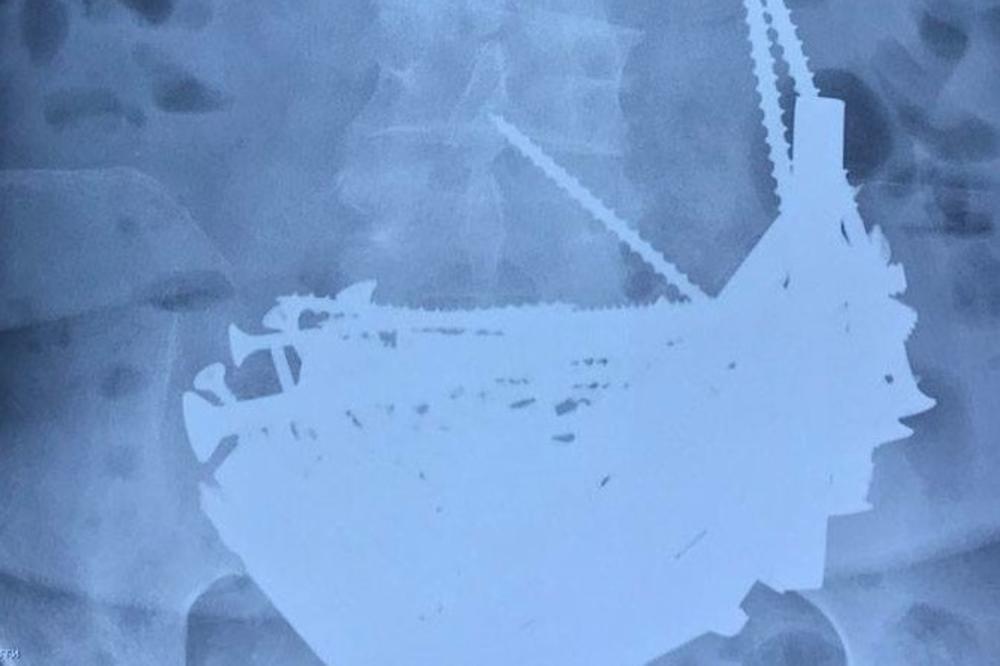

Stalno prisutra povišena temeratura je navela doktore da ipak urade gastroskopiju. Nakon pregleda ustanovili su da je jednjak i grlo u redu, ali je endoskom otkrio nešto neobjašnjivo. U želudcu pacijenkinje našli su pregršt metalnih predmeta: šrafova, eksera, matica, delova armature čak do 15cm.

Iz želudca pacijentkinje operacijom su izvađeni ekseri, veliki šrafovi, matice, reze za vrata, delovi armature dugi do 15 centimetara, pa čak i srebrni lančić finoće 925. Ukupno 152 metalna predmeta.